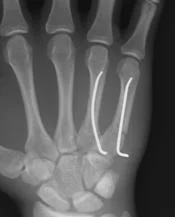

Displaced and proximal fractures

- Internal fixation with special screw